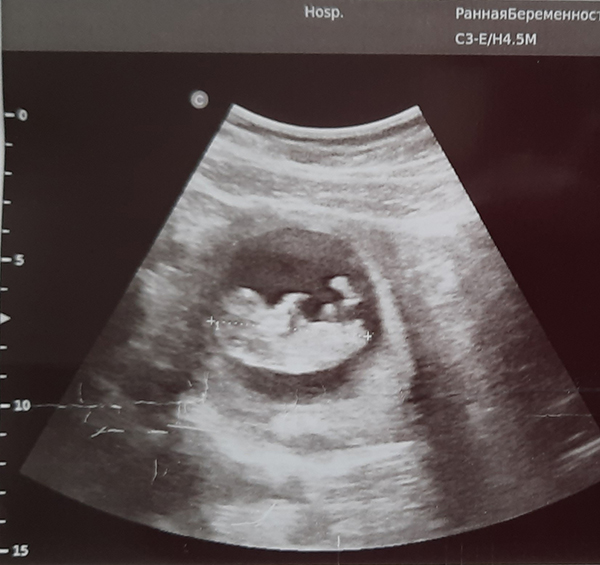

– Смотрите, на что похоже? – наконец поворачивая ко мне экран, задаёт очередной вопрос доктор.

Напряжённо вглядываюсь в чёрно-белое изображение своего богатого внутреннего мира, ожидая увидеть там что-то по меньшей мере неприятное (иначе, к чему весь этот допрос?!) Секунда, другая... И вдруг – совершенно чёткое и спокойное осознание: вон то едва заметное пятнышко, похожее на запятую, – это маленькая жизнь. И она – внутри меня, где-то под сердцем…

– 10-11 недель беременности, – подтверждает доктор. И добавляет: